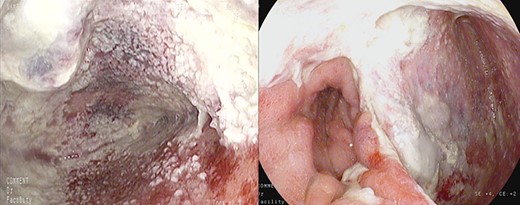

Large anastomotic leakage after minimally invasive esophagectomy opening to a cavity in the pleural space of 8 cm in size.

On the third postoperative day (POD), inflammatory indexes increased (CRP 178.2 ng/mL). On the fourth POD, the endoscopy and CT scan showed a large anastomotic leak involving 75% of the anastomosis and opening to a giant wound cavity in the pleural space of 8 cm in size; fibrosis and abundant necrotic tissue were also present (Fig. 1).